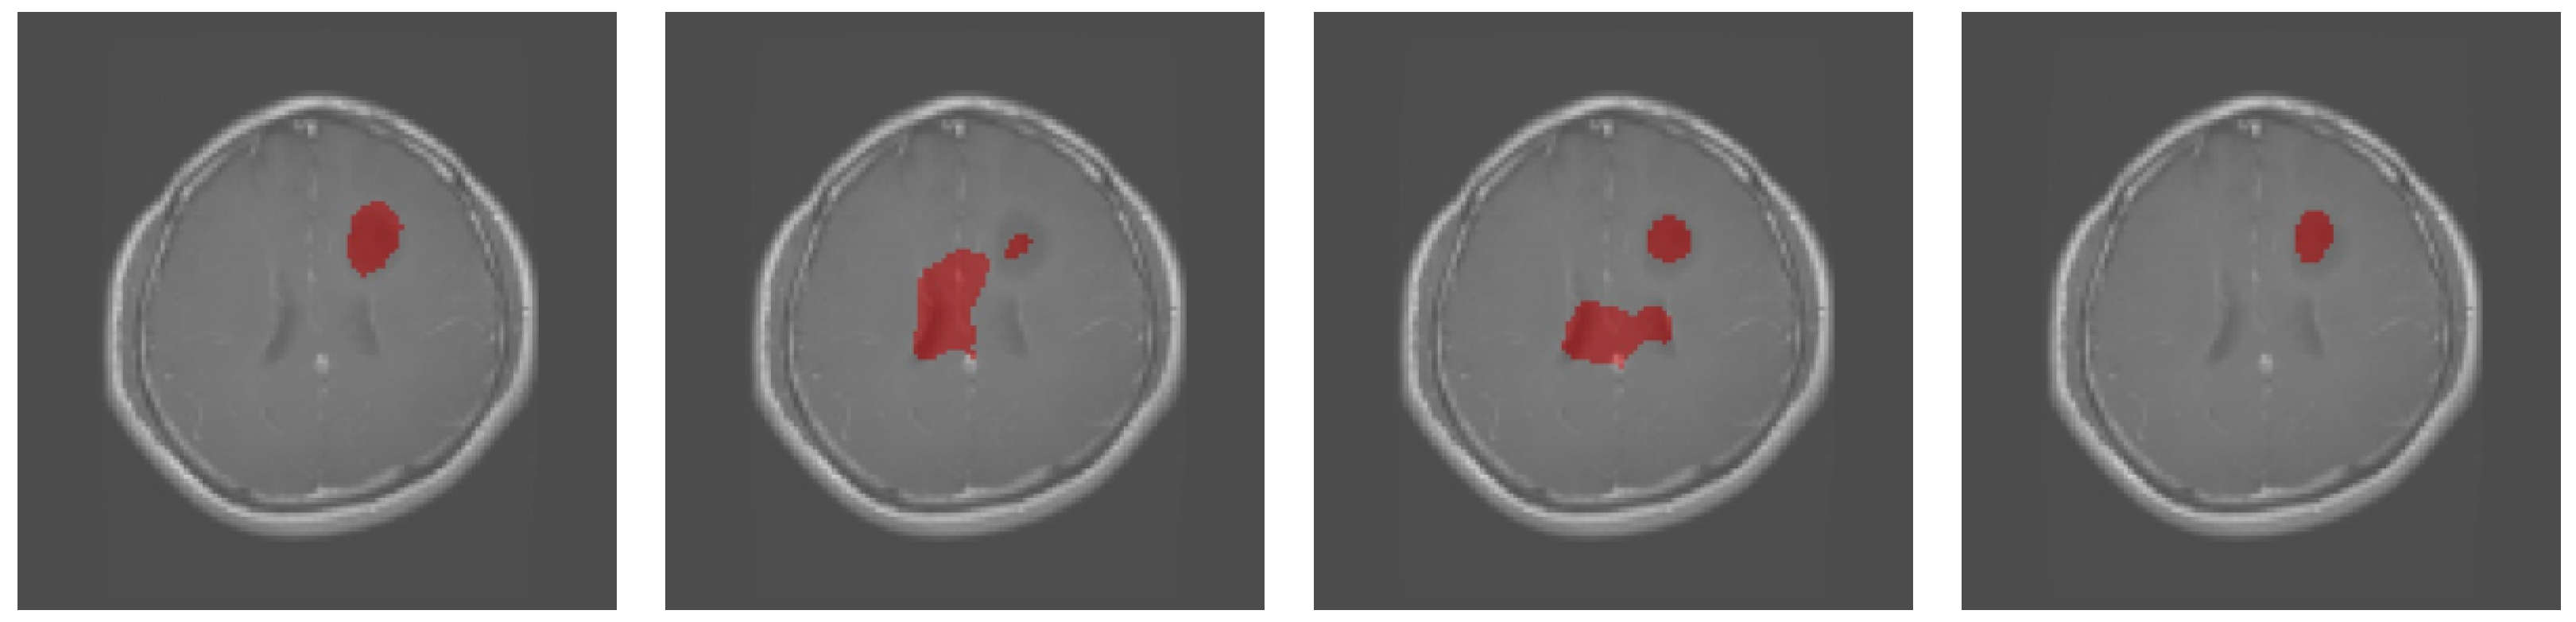

Figure 2 shows the qualitative results obtained on the sample test images from the Brain MRI dataset. U-Net had a rather high misclassification rate. Some details and object boundaries were precisely obtained with Att-UNet, but the central areas were misclassified as gliomas. In contrast, most of the categories that were misclassified by other methods were correctly classified by SAB-Net. This supports our claim that integrating all of the proposed operations lets the network learn context information. Thus, the proposed methods enhanced the discrimination of details and improved the semantic consistencies for the segmentation tasks involving this Brain MRI dataset.

Figure 2.

Qualitative results obtained for the brain MRI images. From left to right: ground truth, U-Net, Att-UNet, and SAB-Net.